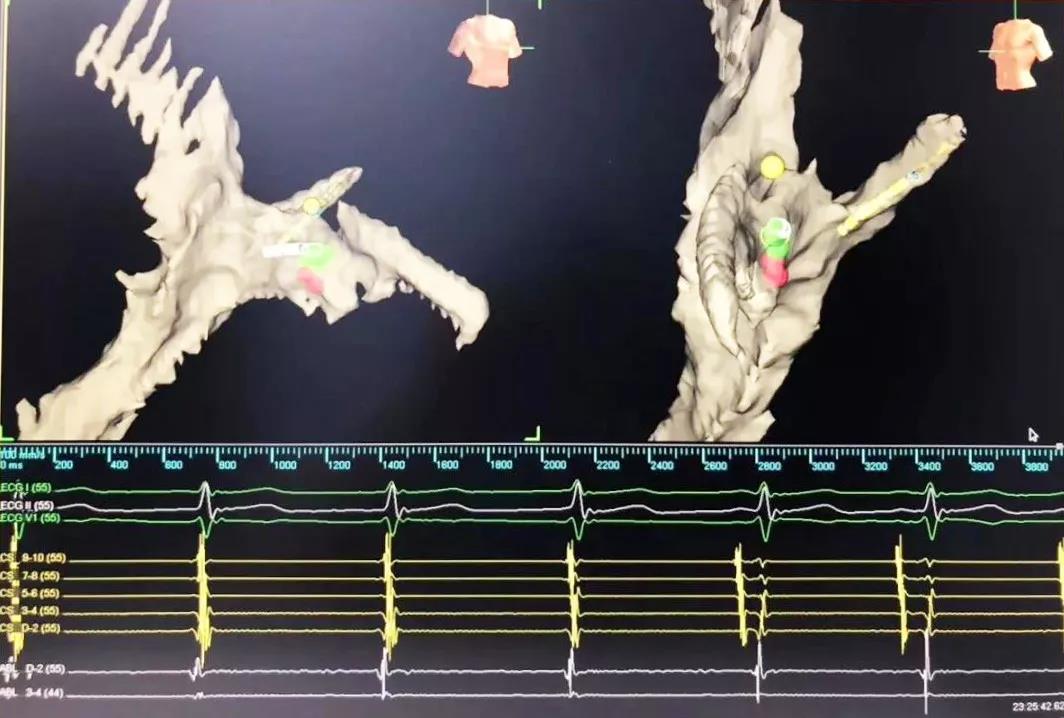

又一道難題擺在眼前,常規(guī)手術(shù)需要在X射線(xiàn)下進(jìn)行,X射線(xiàn)會(huì)導(dǎo)致胎兒發(fā)育畸形。在心臟病醫(yī)院院長(zhǎng)王海昌的帶領(lǐng)下,專(zhuān)家團(tuán)隊(duì)仔細(xì)研究后,決定為張女士施行三維標(biāo)測(cè)系統(tǒng)指引下零射線(xiàn)心臟電生理檢查及射頻消融術(shù)。

在完成常規(guī)檢查,排除新型冠狀病毒肺炎的可能后,217日,由廉誠(chéng)主刀,在三維標(biāo)測(cè)系統(tǒng)指引下行零射線(xiàn)心臟電生理檢查及射頻消融術(shù)。術(shù)中明確患者心動(dòng)過(guò)速為房室結(jié)折返性心動(dòng)過(guò)速,遂行房室結(jié)慢徑改良,消融完畢后反復(fù)刺激驗(yàn)證,心動(dòng)過(guò)速均不能誘發(fā),手術(shù)成功,歷時(shí)約1小時(shí),全程零射線(xiàn)完成。這也是西安國(guó)際醫(yī)學(xué)中心醫(yī)院心臟病醫(yī)院的首例零射線(xiàn)治療特殊人群心律失常病例。